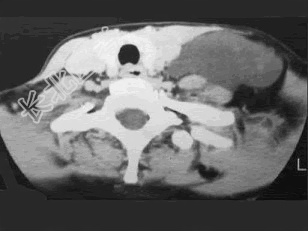

- 多项选择题37岁女性,左侧颈部肿块渐进性增大, 无压痛,局部皮温不高, CT、MRI扫描如图所示,请选择正确的描述或诊断 ( )

A、CT发现左侧颈后三角区可见低密度肿块影

B、增强扫描未见强化

C、MRI的T

WI呈低信号D、MRI的T

WI呈高信号,其内可见分隔E、考虑为淋巴管囊肿